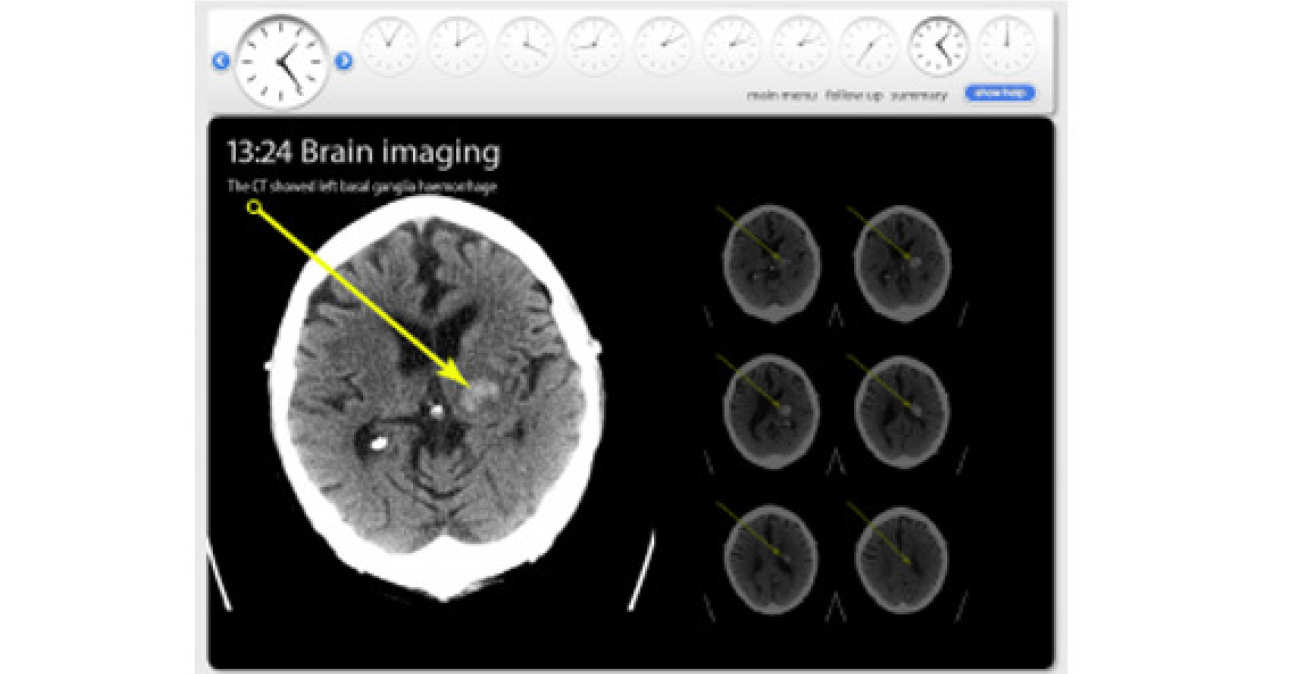

Stroke involves a disruption of blood supply to the brain, causing cell death. The disruption can be due to a blockage of an artery (ischaemic stroke) or due to the bursting of an artery (haemorrhagic stroke). It is estimated that there are over 100,000 strokes per year in UK with more than half of patients having disability arising from the stroke. Stroke units save lives: stroke patients in general wards have 14-25% higher mortality than patients in dedicated stroke units. These are the main causes for ischaemic stroke: cardioembolic, actherothromboembolism, small vessel disease and haematological disease.

The primary aim was to implement an e-learning package to ensure that the workforce in the London Hyper-Acute and Stroke Rehabilitation Units are fully trained using a wide range of teaching resources. The electronic-learning module shown is an edited version of a module that was deployed to enable all members of the multi-disciplinary team have access to training material. The module was developed in conjunction with stroke physicians, nurses, speech and language therapists, physiotherapists and occupational therapists on the ward. There was also input from the London Ambulance Service and GP’s to ensure that those health-care workers who may come in contact with stroke outside the hyper-acute setting can understand the issues relating to stroke diagnosis and treatment in the hospital.

Permission was obtained to film patients and staff throughout their journey on the stroke pathway. This involved the initial emergency assessment, imaging and access to the patient’s medical record. These resources were then edited into ‘scenarios’ which the staff used to help understand various aspects of acute stroke diagnosis and management. The scenario shown is for a brain haemorrhage. A total of nine distinct scenarios were produced and validated.